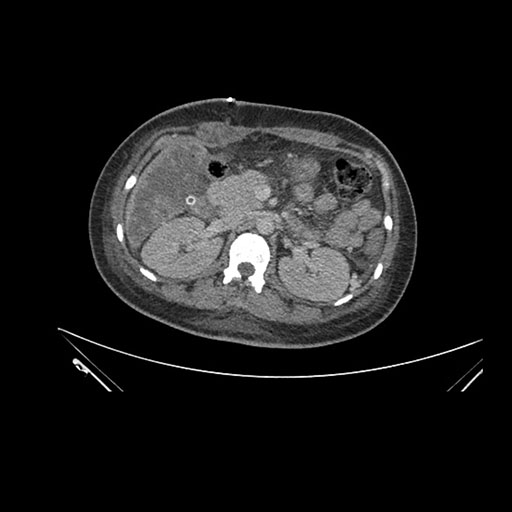

Axial Venous